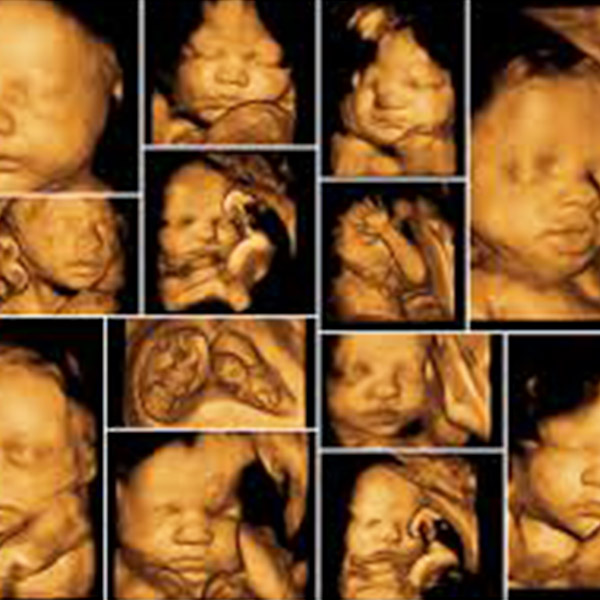

40'Tan Fazla Kadına Aynı Ultrason Görüntüsü Verildi!

Bir annenin Facebook’ta dolanırken, bebeği ile aynı ultrason görüntülerini paylaşan başka bir kadına rastlaması, akıl almaz bir skandalı ortaya çıkarttı. Şili’de görev yapan Kadın Hastalıkları ve Doğum uzmanı Dr. Eduardo Olivia, olayın duyulmasıyla 40’tan fazla kadına aynı ultrason görüntüsü verdiğini itiraf etti.

Şili’de yaşayan Belen Aguilera adlı kadın, Facebook’ta dolanırken kızının ultrason görüntülerine benzeyen başka bir ultrason görüntüsüyle karşılaşıyor. Emin olmak için kızının ultrason görüntüsüyle karşılaştıran Aguilera, görüntülerin tıpa tıp aynı olduğunu fark ediyor. Fotoğrafın 6 yıl önce başka bir kadına verildiğini öğrenen Aguilera, olayın üzerine düşünce aynı görüntünün 7 yıl önce verildiği başka bir anneye daha ulaştı.

Konu hakkında Facebook’tan bir gönderi paylaşan genç anne, yaklaşık 23.000 etkileşim aldı ve aynı sorundan muzdarip olan diğer kadınlara ulaşmayı başardı. İnsanın duygularıyla oynayan, aileleri yanıltan ve özel görüntüleri başkasıyla paylaşan doktorun onlarca kişiyi sarstığını dile getiren Belen Aguilera, diğer annelerin durumdan haberdar olduğunda nasıl hissedeceklerini düşünmek bile istemediğini belirtti.

Her anne adayına yapılan temel 2D görüntülerin doğru bir şekilde verildiğini belirten Dr. Olivia, pahalı olan 3D görüntülerde, tarayıcıdan kaynaklanan hata nedeniyle yanlışlık olduğunu iddia etti. Şili medyası, 3D görüntünün ülkede ortalama 50 bin peso, (54 Euro) olduğunu yazdı. Tıp Fakültesi Dekanı Izkia Siches ise iddiaların doğru olması durumunda doktorun lisansının iptal edilebileceğini açıkladı.